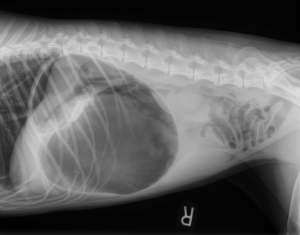

A prophylactic gastropexy is a preventive surgical procedure that tacks the stomach to the abdominal wall to stop it from twisting. This twist, known as Gastric Dilatation Volvulus...